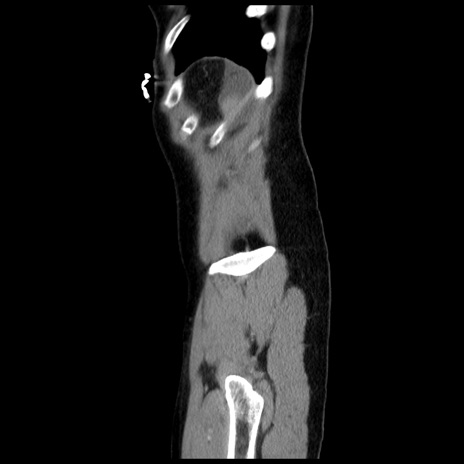

症例10(矢状断像)

【症例】 50歳代女性

【主訴】 腹痛

【現病歴】前日生レバーを食べた。今朝に排便あり。 昼前に突然発症の腹痛を生じ、当院救急外来を受診した。

【既往歴】 子宮筋腫にてで子宮全摘後

【身体所見】 意識清明、腹部:平坦、軟、下腹部やや左を中心に圧痛・反跳痛あり、筋性防御あり

【データ】WBC 7800、CRP 0.07